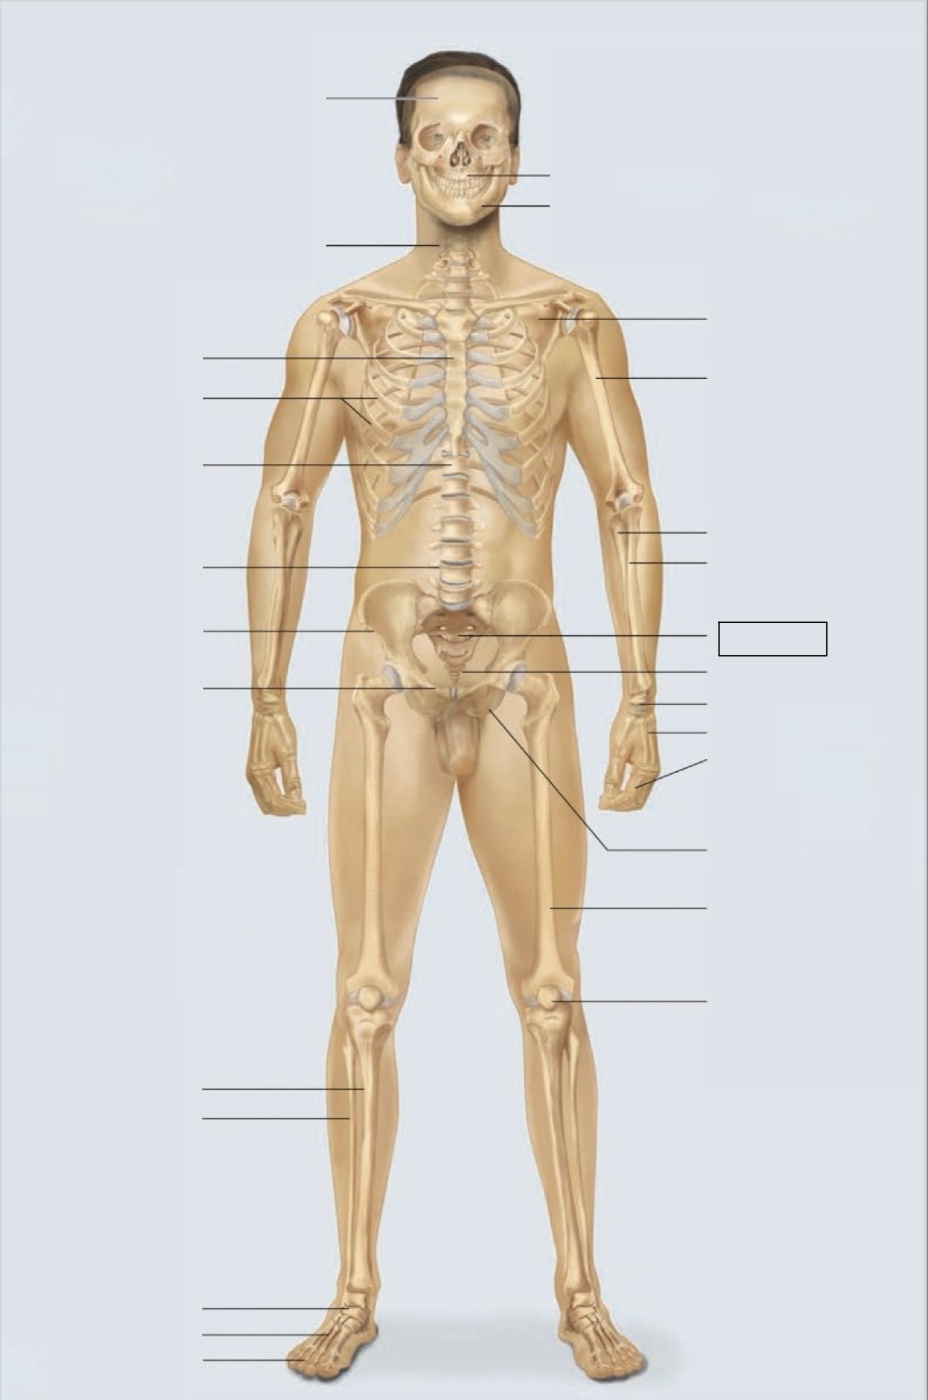

maxilla

mandible

scapula

humerus

ulna

radius

sacrum

coccyx

carpals

metacarpals

phalanges

ischium

femur

patella

phalanges

metatarsals

tarsals

fibula

tibia

pubis

ilium

lumbar vertebrae (L4)

thoracic vertebrae (T11)

ribs

sternum

cervical vertebrae

skull